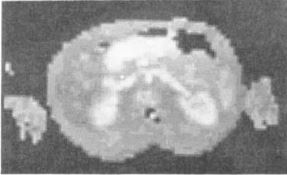

《1988-Time-of-flight法MRA》

図17.膝窩動脈分岐部のTOF法MRA.最大値投影法(MIP)による表示.

【要旨】スピンエコー法のパルス系列では,血管は様々な輝度を示すが,これはボクセル内のスピンの位相が速度に応じて異なるためである.そこで,3つの傾斜磁場から成る速度補償傾斜磁場を追加して定速度スピンをリフェーズするGMR(gradient motion refocusing)法を考案した.これを用いると,定速度スピンはリフェーズされて静止スピンと同じ輝度になる(フロー増強画像).さらにフローを積極的にディフェーズして血管を低信号とする画像を作る(フロー抑制画像).前者から後者をサブトラクションすることにより,バックグラウンドを抑制した血管画像が得られる.この方法で動脈は収縮期にはリフェーズできず,拡張期にリフェーズするので,前者から静脈像,後者から動脈像が得られる.

GMR法をFLASHと組合わせると,TEが短いためにゲートが不要で,TRが短いため撮像時間も短縮して3D撮像が可能である(図17).この場合も,フローをリフェーズしたデータセットからディフェーズしたデータセットをサブトラクションする.得られた画像の表示法として,撮像ボリュームに平行光線を入射して,経路上の最大値を画像とする最大値投影法を提案した.これにより血管像のシネ表示も可能である.

【解説】MRAの初報は,この2年前のDumoulinによるPhase contrast法であったが,本稿はTOF法によるMR血管撮影(MRA)の初報である.ただここで論じているのは,単純にTOF効果(流入効果)を利用するものではなく,フロー補正傾斜磁場(GMR)を併用し,かつサブトラクションを行なう方法である.その意味で,TOF法MRAの初報であると同時に,現在は主にgradient moment nulling (GMN) あるいは flow compensation (FC)と呼ばれている速度項補正法の初報でもある.さらに,現在MRAの表示法として広く使われている最大値投影法(MIP)を初めて提案している点でも,その後のMRAのスタート地点となった論文である.